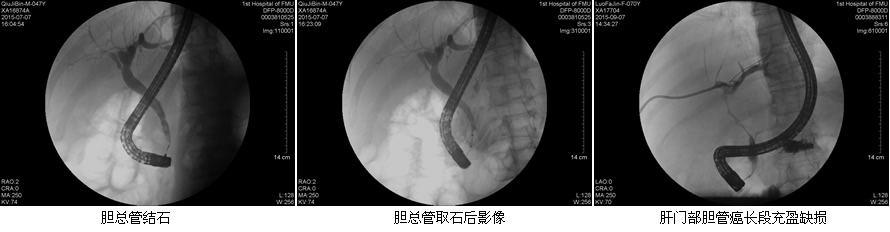

目前ERCP适应症主要包括:原因不明的阻塞性黄疸疑有肝外胆道梗阻者;疑有各种胆道疾病如结石、肿瘤、硬化性胆管炎等诊断不明者;疑有先天性胆道异常或胆囊术后症状再发者;胰腺疾病:胰腺肿瘤、慢性胰腺炎、胰腺囊肿等。在这50余例病例中,包含了内镜下乳头活检术、乳头括约肌切开取石术、胆管内支架引流术、鼻胆管引流术、“三镜”联合治疗胆总管结石等,患者术后无明显并发症发生,获得了良好的疗效,使我院ERCP诊疗技术进入一个崭新的时代。

在工作中,该团队始终坚持“用科研的态度对待每一例患者!”无论是小小的十二指肠乳头活检术,还是难度较大的胃毕Ⅱ术后乳头切开取石术,乃至肝门部高位胆管癌内支架置入术,“安全至上”的理念始终体现在每一位患者身上。无论简单还是复杂,ERCP团队的每一位成员,术前都严格评估适应症和禁忌症,术中规范操作,术后应按预案防治并发症,确保了每一例患者的安全。